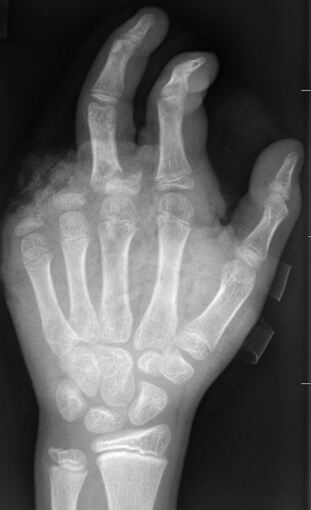

In der Handchirurgie müssten an Silvester im Unfallkrankenhaus rund 20 bis 40 Menschen mit Böllerverletzungen operiert werden, sagt die Ärztin. Dieses Jahr werde sie mir vier weiteren Handchirurgen im Einsatz sein. Die häufigsten Verletzungen entstünden durch explodierende Böller in der Hand.

«Der überwiegende Teil der Verletzungen trägt tatsächlich lebenslange Folgen mit sich, weil die Sprengkraft dazu führt, dass eben nicht nur einzelne Strukturen verletzt sind, sondern immer mehrere. Und das heilt praktisch nie ganz folgenlos ab.» Zum Teil könnten Hände nicht mehr gerettet und müssten amputiert werden.